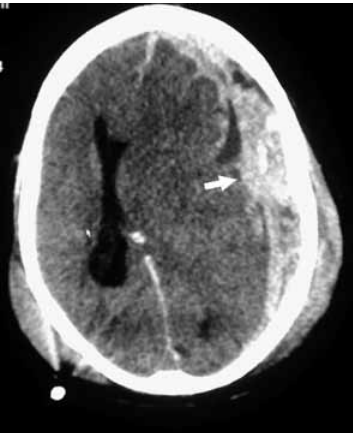

Analise a imagem tomográfica.

O diagnóstico correto é: